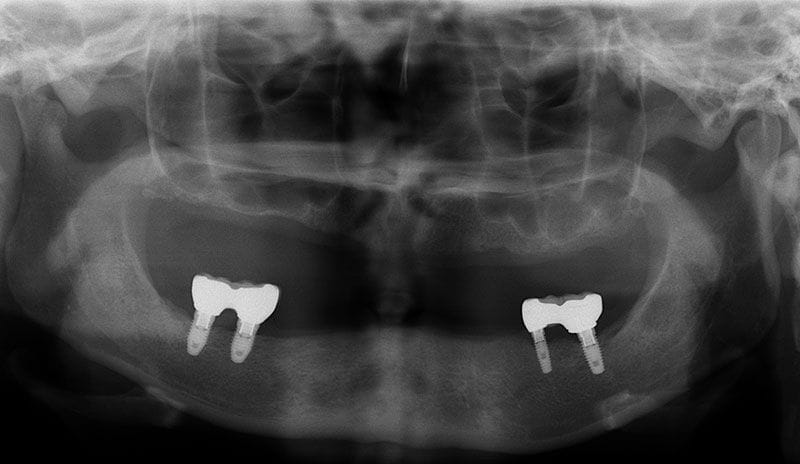

植牙的目的,就是將原來已經失去的咬合能力復原,因此必須更謹慎的評估患者骨質的密度、高度和寬度是否都能滿足植牙的條件。